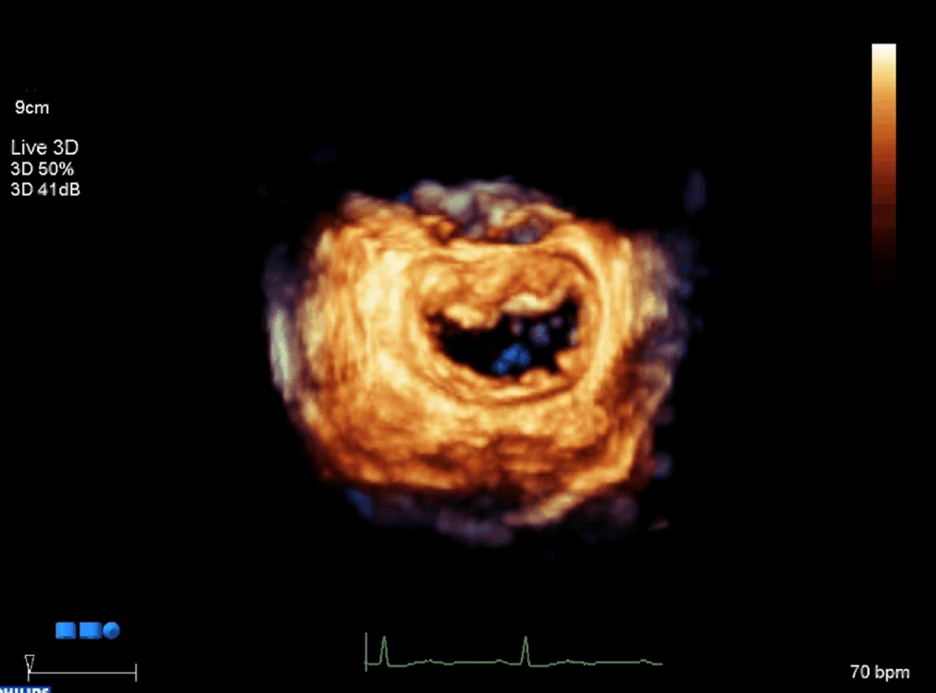

- Ecocardiograma 3D intraoperatório

O INC conta com equipamentos de última geração e profissionais altamente capacitados na área de ecocardiografia, o que auxilia no resultado ótimo das intervenções cardíacas estruturais.

Válvula mitral vista pelo ecocardiograma 3D